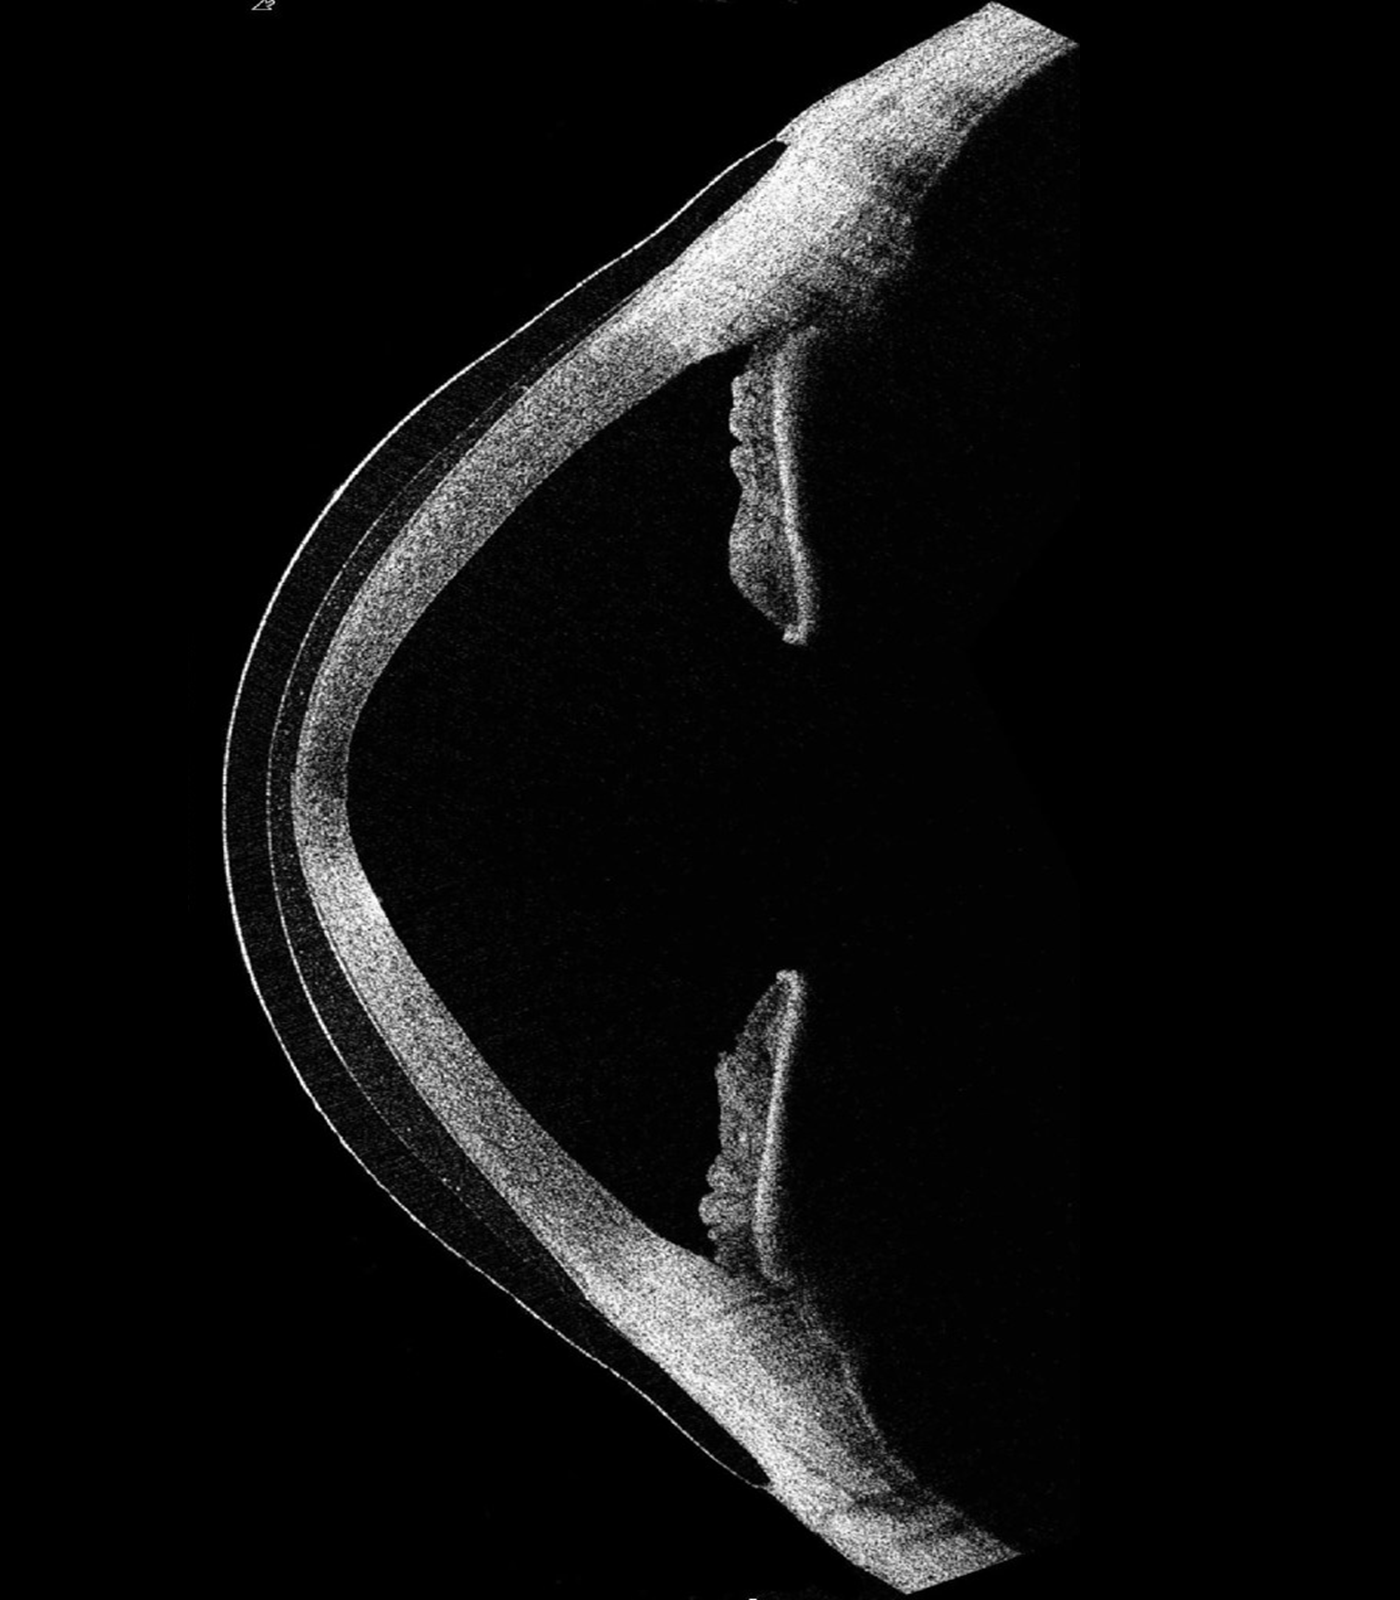

Conditions distorting the eye's front surface causes incoming light rays to scatter, resulting in vision problems that can't be corrected using a standard approach. In such cases, EyeSpace Scleral lenses act like a prosthetic to replace the eye's irregular surface, correctly focusing incoming light rays and restoring optimum vision. In addition, it also provides a water bath to the eye, making it a successful treatment option for dry eyes.

Not a good soft lens candidate or have an unusual eye shape? Bespoke corneal RGP might be the right option for you. People with irregular corneas from disease, surgery or trauma, or complex prescriptions like astigmatism often find glasses and soft contact lenses still leave them with distorted vision. Bespoke corneal RGP lenses are individually tailored for your eyes, neutralising the distortion to give back your clarity of vision.

No matter how unique your eyes are. Our Bespoke corneal RGP lenses are purpose-made based on advanced imaging that maps every contour of your eye. Each lens is engineered to be as unique as you are. To fit like a glove and feel like it.